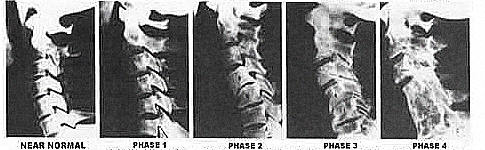

Osteoarthritis or DJD is an inflammatory condition of the joint that causes pain, swelling and lack of movement.  It can affect any joint, big or small, and if left untreated, can lead to complete breakdown and eventually fusion of the joint.

Saying that, joint surfaces can wear down—the cartilage breaks down, little by little, until the plate gets worn to the bone (think of a worn down pencil eraser for lack of a better analogy).  When this happens, the pain that accompanies movement of that particular joint can be excruciating.

But it doesn’t happen so innocuously.  Degeneration is a time process, and along the way inflammation sets in, with its cardinal signs of heat, redness, swelling, pain, and loss of function.  Let me emphasize one point: LOTS OF PAIN!  I always say, “Want to see a grown man cry?  Observe a man with arthritis in his neck.”  Really, it’s tough to witness.

An all too common form of non-movement affecting the joint in a similar but perhaps even worse way than being sedentary is the subluxation.  Subluxations, you’ll remember from my earlier articles, is a non-moving joint.  Recall that joint surfaces can stick together preventing lubrication and locking-up the joint itself.  Both non-lubrication and non-movement together are disastrous for the joint cartilage.  This is when the body will start an auto-breakdown of the joint in an attempt to form a non-moving structure.  Although it may seem unintelligent for the body to create a non-moving structure out of an existing moving part, deeper thought unveils that the body doesn’t know the difference between conscious and unconscious inactivity—it only knows that moving parts are meant to move, period!  When this doesn’t happen freely and regularly, why would the body exert energy and raw materials to maintain it as a moving part?